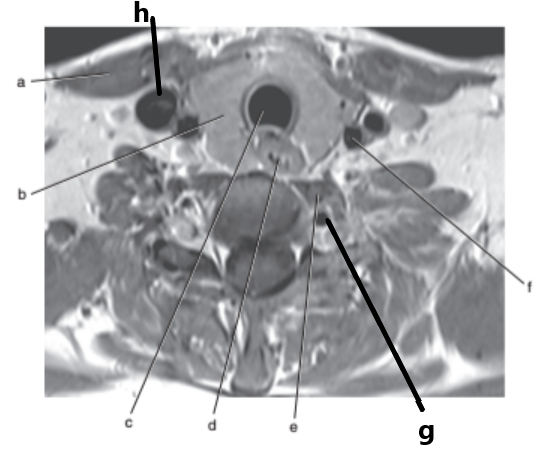

Vertebral artery

Internal jugular vein

Spinal cord